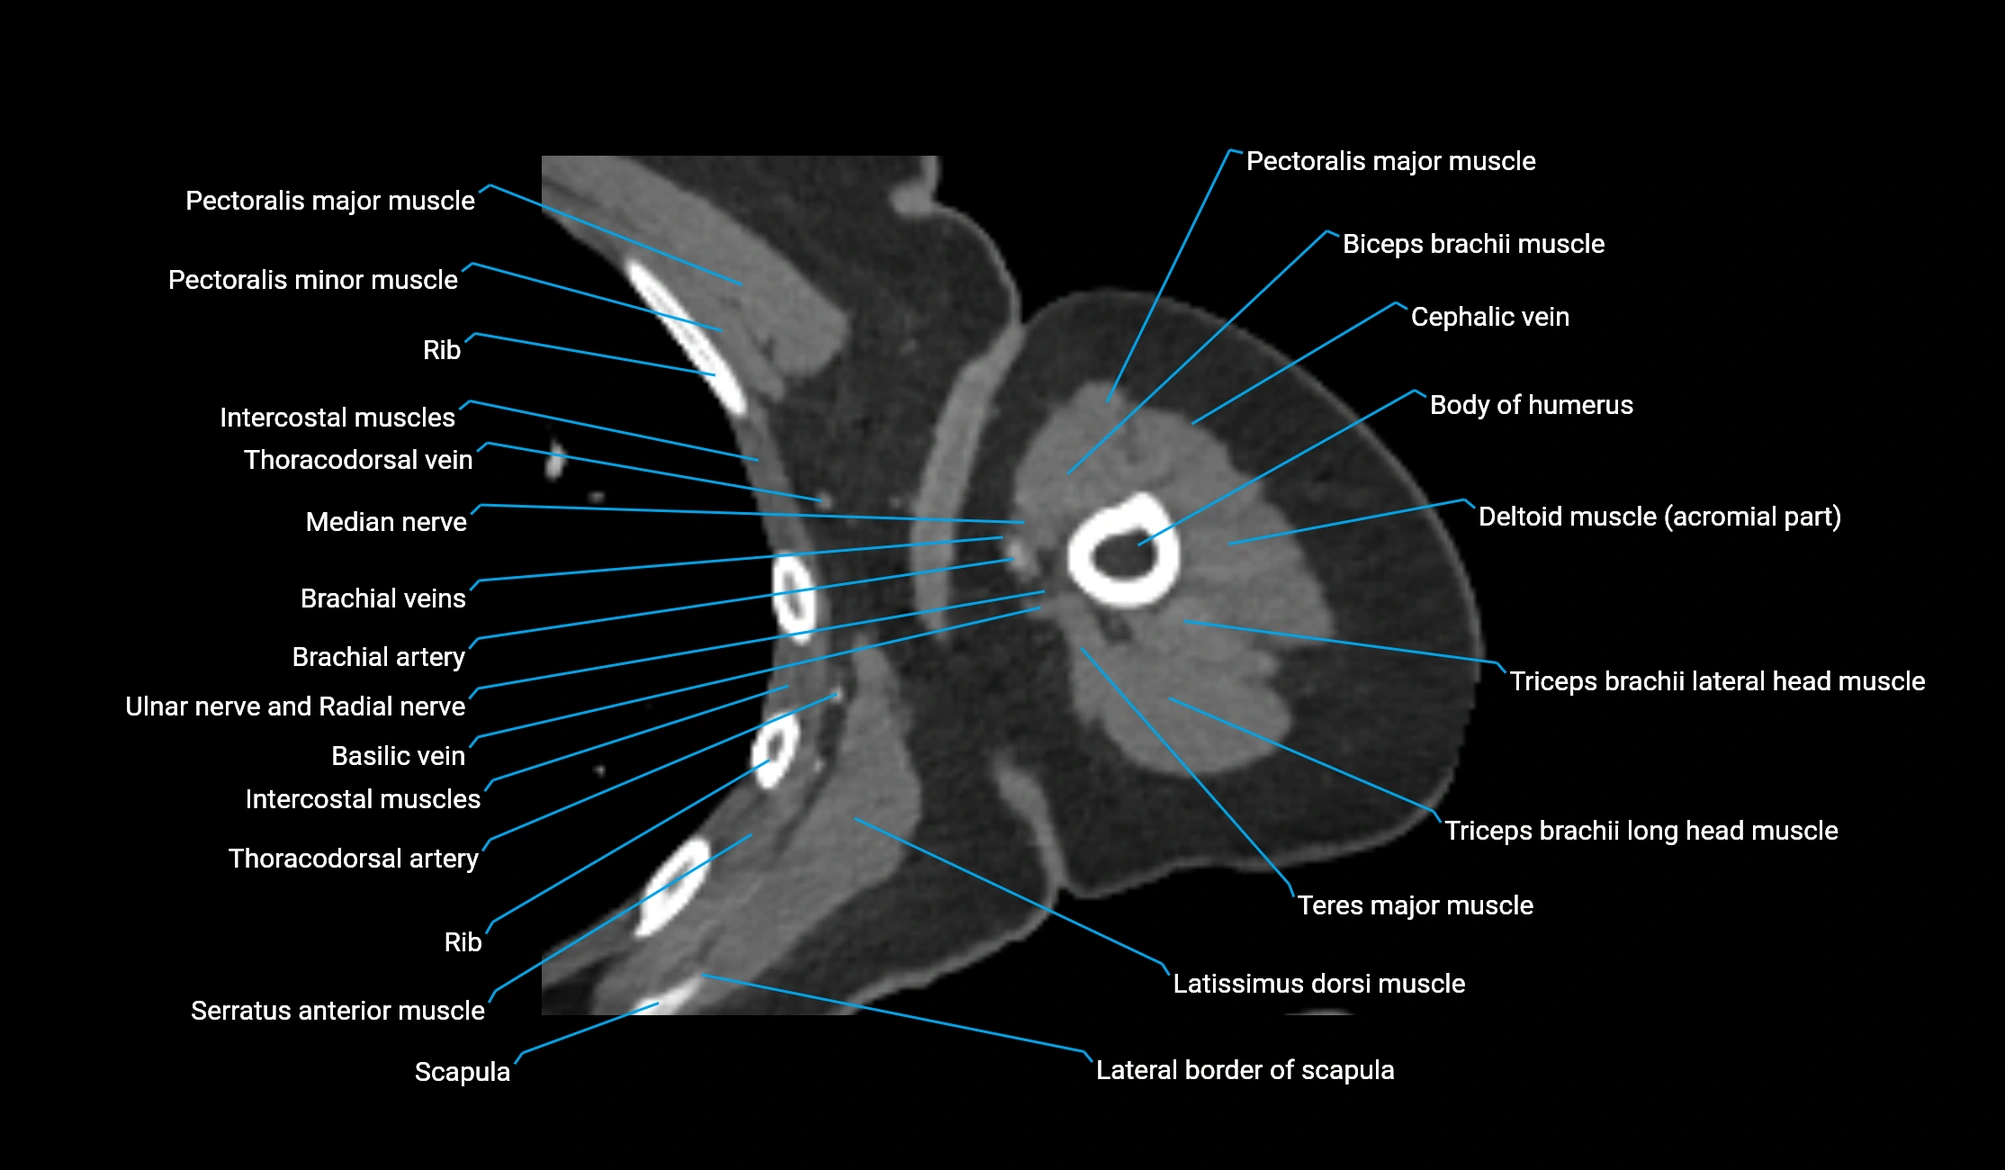

- Body of humerus

- Cephalic vein

- Pectoralis major muscle

- Pectoralis minor muscle

- Teres major muscle

- Thoracodorsal artery

- Triceps brachii muscle